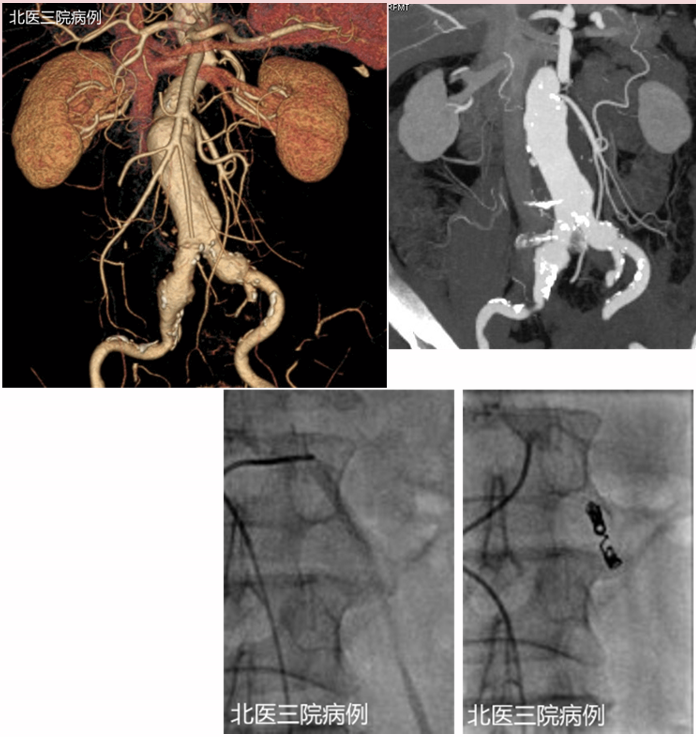

★ Case 2

II型内漏 预防:预栓腰A

预栓粗大肠系膜下、腰动脉

动脉瘤囊腔填塞